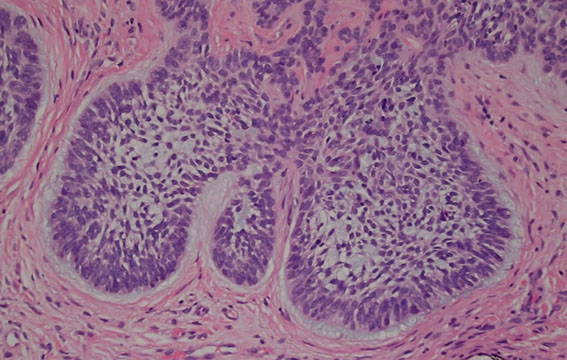

Trichoblastoma

An adnexal tumor made of ribbons of basaloid cells with basaloid islands, clefts bwt collagen, concentric fibroblastic rich stroma with no retraction

Micro: cells can look a lot like BCC, but the stroma has concentric fibroblast-rich collagen

- papillary mesenchymal bodies can be in the stroma, but mucin will never be in stroma (mucin only within tumor islands)

Lymphadenoma

- aka adamantinoid trichoblastoma

Variant of trichoblastoma with blue tumor islands that have up to 2 layers of peripheral basal cells

- center of the islands are pale due to clear cells and inflammatory cells (lymphocytes and histiocytes)

- fibroblast-rich stroma with no retraction

Tx/Px: B9, just needs F/U

Cutaneous lymphadenoma